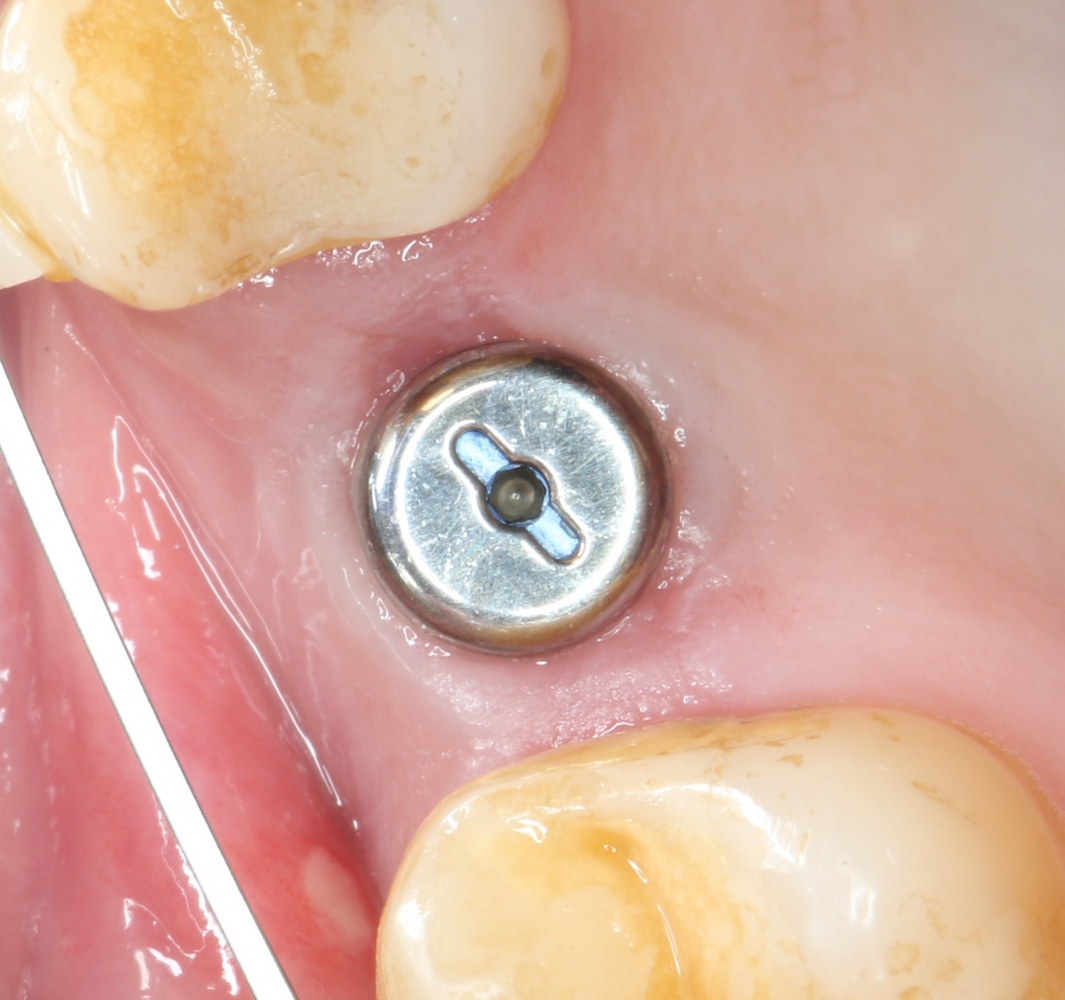

Синуслифтинг: что делать при перфорации слизистой оболочки гайморовой пазухи?